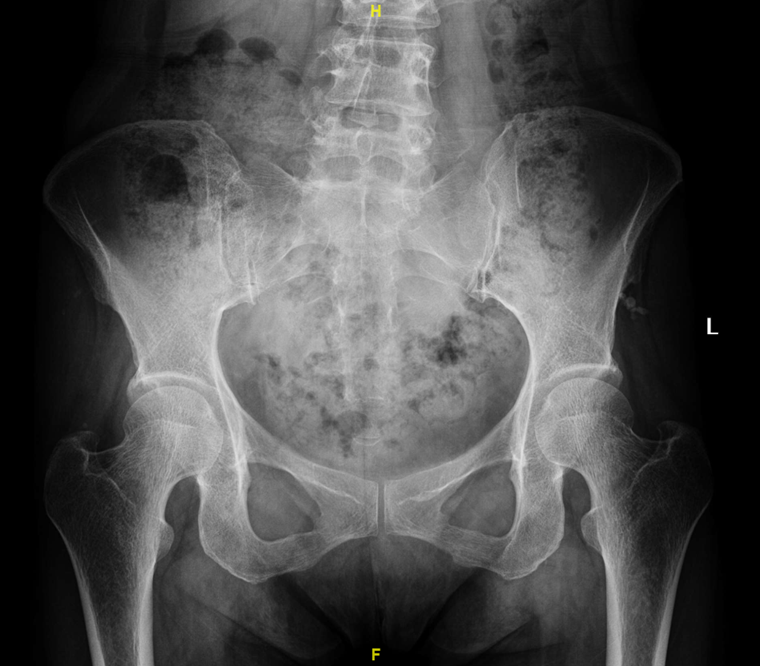

正常-成年人双侧髋关节正位X线片

典型-双侧髋关节发育不良的X线片

双侧髋关节发育不良-轻度-X线片,患者因双膝关节骨关节炎住院拟行膝关节置换手术治疗前,行双下肢全长正位X线片检查时发现髋臼发育不良(先髋,DDH),但查体和病史询问,患者无髋部疼痛症状,故不做任何治疗